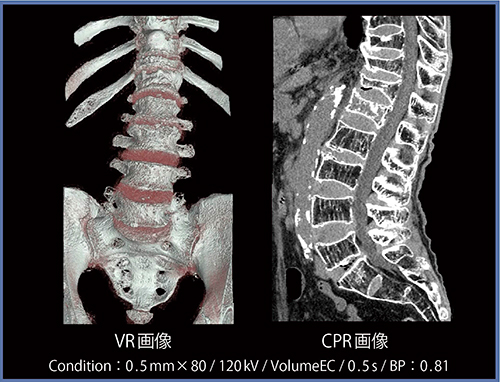

FIRSTではアンダーシュートが低減され,のっぺりした印象となるため,導入当初はAIDR 3Dとの見え方の違いに戸惑うこともあった(図1)。また,FIRSTでは,骨の表面がややザラザラとした画像となるものの,VR画像は分解能を保持したまま作成でき,CPR画像はウインドウ変更のみで脊髄など軟部組織の観察が容易となる(図2)。

図2 症例1のFIRST Body Standardを用いた三次元画像処理例